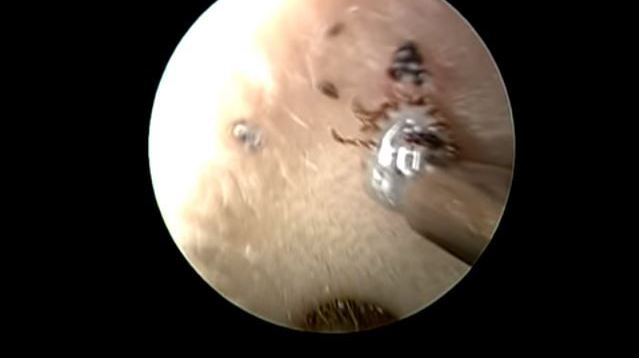

La garrapata se aferraba a la piel. Crédito: YouTube

En el video se ve cómo el doctor primero usa una herramienta con la cual pretende succionar a la garrapata, pero esta se aferró a la piel del paciente e incluso se ve cómo aumenta de tamaño debido a la cantidad de sangre que ya le había extraído.

Finalmente, decide usar unas pinzas con las cuales, finalmente logra sacar al animal.